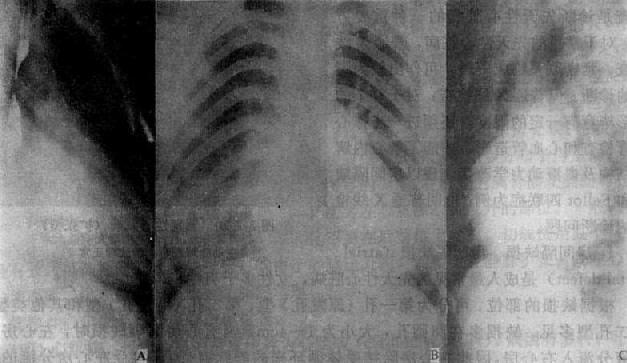

Fallot四联症

图3-2-22 Fallot四联症

心增大,心尖圆钝上翅,心腰平直,右心室增大,

肺门缩小,肺纹理纤细,稀少